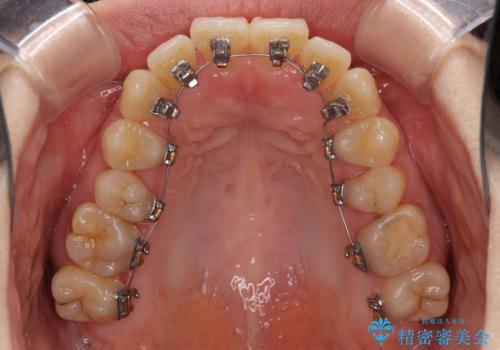

下顎の歯列全体を後方に動かす場合、さまざまリスクを伴うため慎重に行う必要があり、さらには移動量に限界があるため、治療計画は無理のないものとしなければなりません。

下顎左右の奥にアンカーボルトを使用して、無理のない範囲で後方に移動させ、きれいに仕上げることができました。